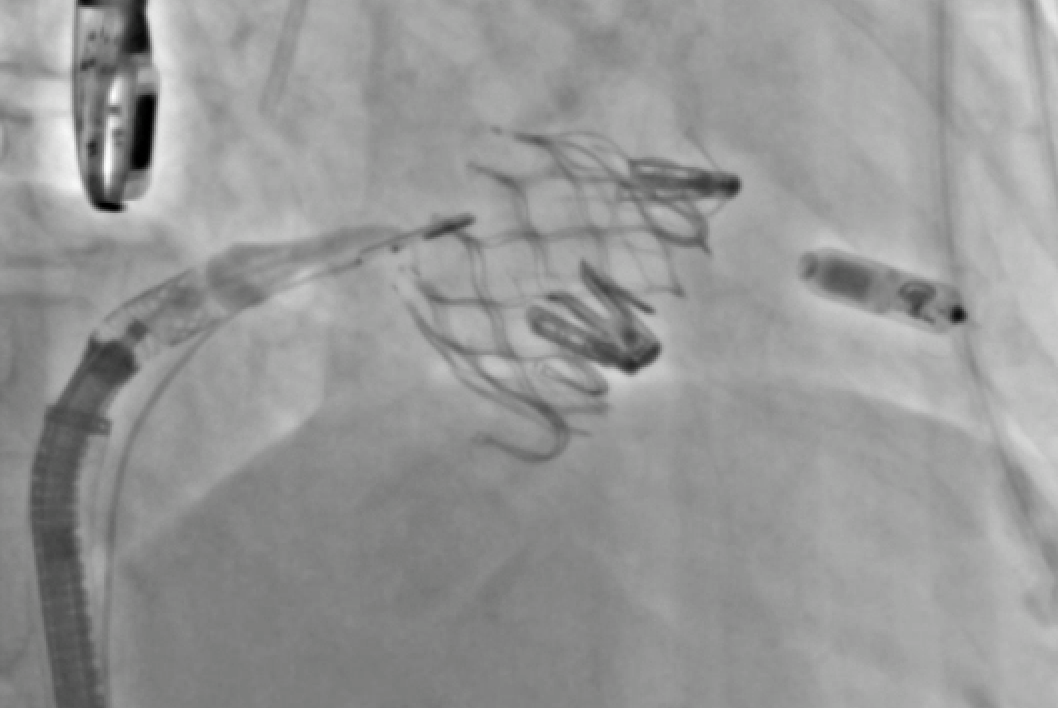

25 days

Just published: Beyond Limits in Alternative Access: The Success of Right Subclavian Transcatheter Mitral Valve Replacement https://t.co/tqabVP6z8e @Brianponeill @PedroMDMSc @engelpedro @GKFram @AhmadJabri8